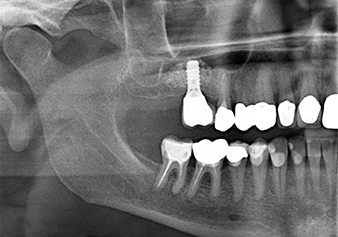

Una paziente di 49 anni, non fumatrice e con un'anamnesi priva di elementi rilevanti, è stata indirizzata al nostro studio di chirurgia orale per l'estrazione chirurgica del dente 16 ed il successivo impianto. Dopo l'estrazione, la paziente ha accusato dei lievi dolori causati dalla sinusite, motivo per cui abbiamo inizialmente aspettato sei mesi prima di procedere con l'intervento. L'altezza ossea residua in corrispondenza della posizione dell'impianto misurava 3-4 mm (Fig. 1 e 2).